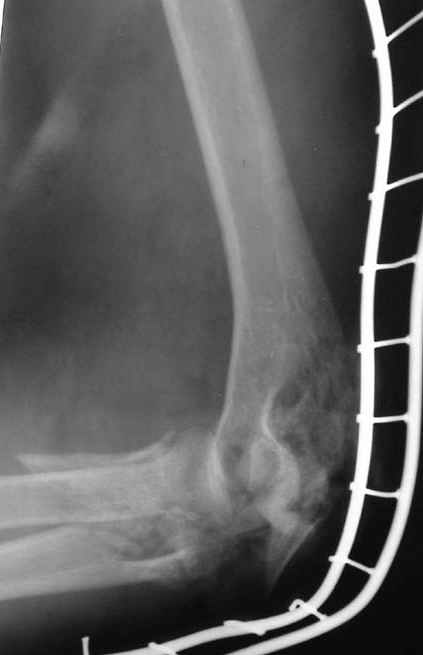

Уважаемые коллеги! Мужчина, 30 лет. В состоянии алкогольного опьянения заснул на рельсах и, по собственным словами, <слегка зацепился за трамвай>.

Обширная почти циркулярная (3/4 рана), в которую выстоят осколки костей с фрагментами суставной поверхности. Обширные ушибы и размозжения мягких тканей вокруг раны. Пульсация на лучевой артерии удовлетворительная, на локтевой слегка ослабленная. Снижение чувствительности в пальцах.Предложения по тактике лечения? Заранее благодарю!!! С уважением,А.В.ВладзимирскийДонецкий НИИ травматологии и ортопедииДонецк, Украина

Операция - ПХО, ЧКО АВФ (см.приложение).

Репонировать фрагменты локтевой и плечевой кости не представилось возможным (по сути <каша> из мелких осколков сомнительной жизнеспособности), резекция головки лучевой кости, иссекли мягкие ткани, кожа зашита почти без натяжения, дренажи, АВФ.